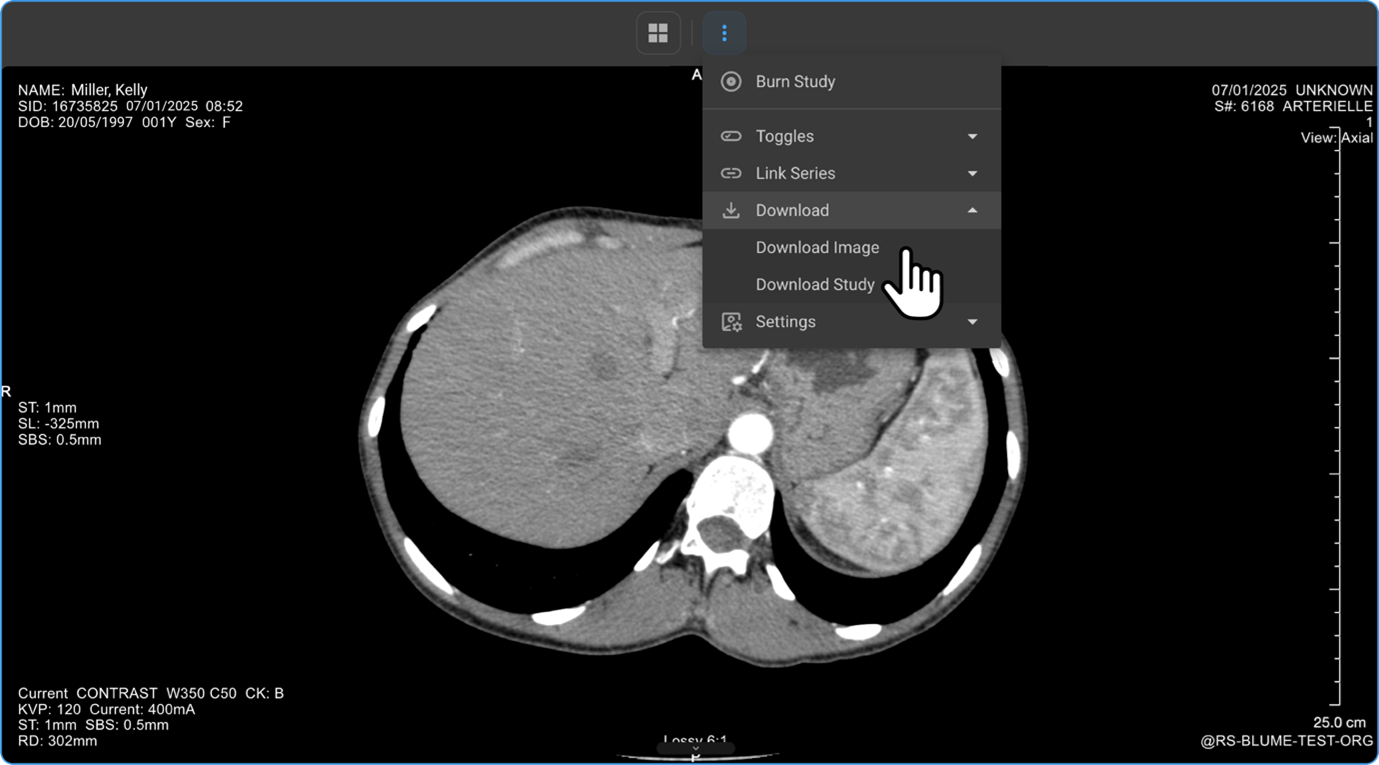

What’s in the More Options (⋮) Ellipsis Drawer Options Menu?

Click the three dots (⋮) on the toolbar to access advanced features:

4. Downloading Studies and Images

1. Downloading Images from the Image Viewer

1. Click View Images to open the Image Viewer.

2. Click the three-dot menu (⋮) in the viewer toolbar.

3. Select Download → Download Image or Download Study.

4. Enter the file name and preferred image resolution (in pixels), then click Download.